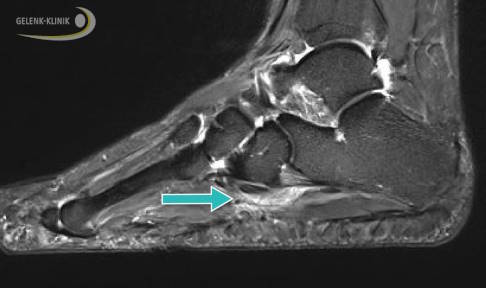

Schmerzhaftes Os-peroneum-Syndrom

Bis zu 25 % der Menschen haben einen zusätzlichen Knochen im Fuß. Dabei handelt es sich um ein Sesambein, das in die Sehne des Musculus peroneus longus eingebettet ist. Meist befindet es sich an der Außenseite des Fußes, dort wo die lange Peroneussehne um das Würfelbein zur Fußsohle zieht.

Bei etwa 60 % der Betroffenen führt der kleine Knochen zu Beschwerden, indem er z. B. die lange Peronealsehne einklemmt oder schädigt. Das kann viele Folgen haben: Die Sehne kann sich entzünden, sie kann aber auch durch vermehrten Verschleiß reißen. Luxationen, also Verlagerungen der Peronealsehne, sind durch den zusätzlichen kleinen Knochen ebenfalls möglich. Die Beschwerden entsprechen der Schädigung. Sie reichen von Ruheschmerzen bis zu Schmerzen beim Gehen, Sehnenschnappen und Instabilität am Sprunggelenk.

Dabei hat die DVT mehrere Vorteile: Sie ist nicht nur strahlungsärmer als das konventionelle Röntgen. Mit ihr lassen sich dreidimensionale Bilder anfertigen, auf denen man die Knochenoberfläche, die Gleitrinne der Sehnen und eventuelle Knochenerhebungen gut erkennen kann. Häufig wird auch eine Kernspintomographie durchgeführt. Sie ermöglicht eine besonders gute Beurteilung der Sehne und des umliegenden Gewebes. Risse, Luxationen und Entzündungen der Sehne können damit gut unterschieden werden.